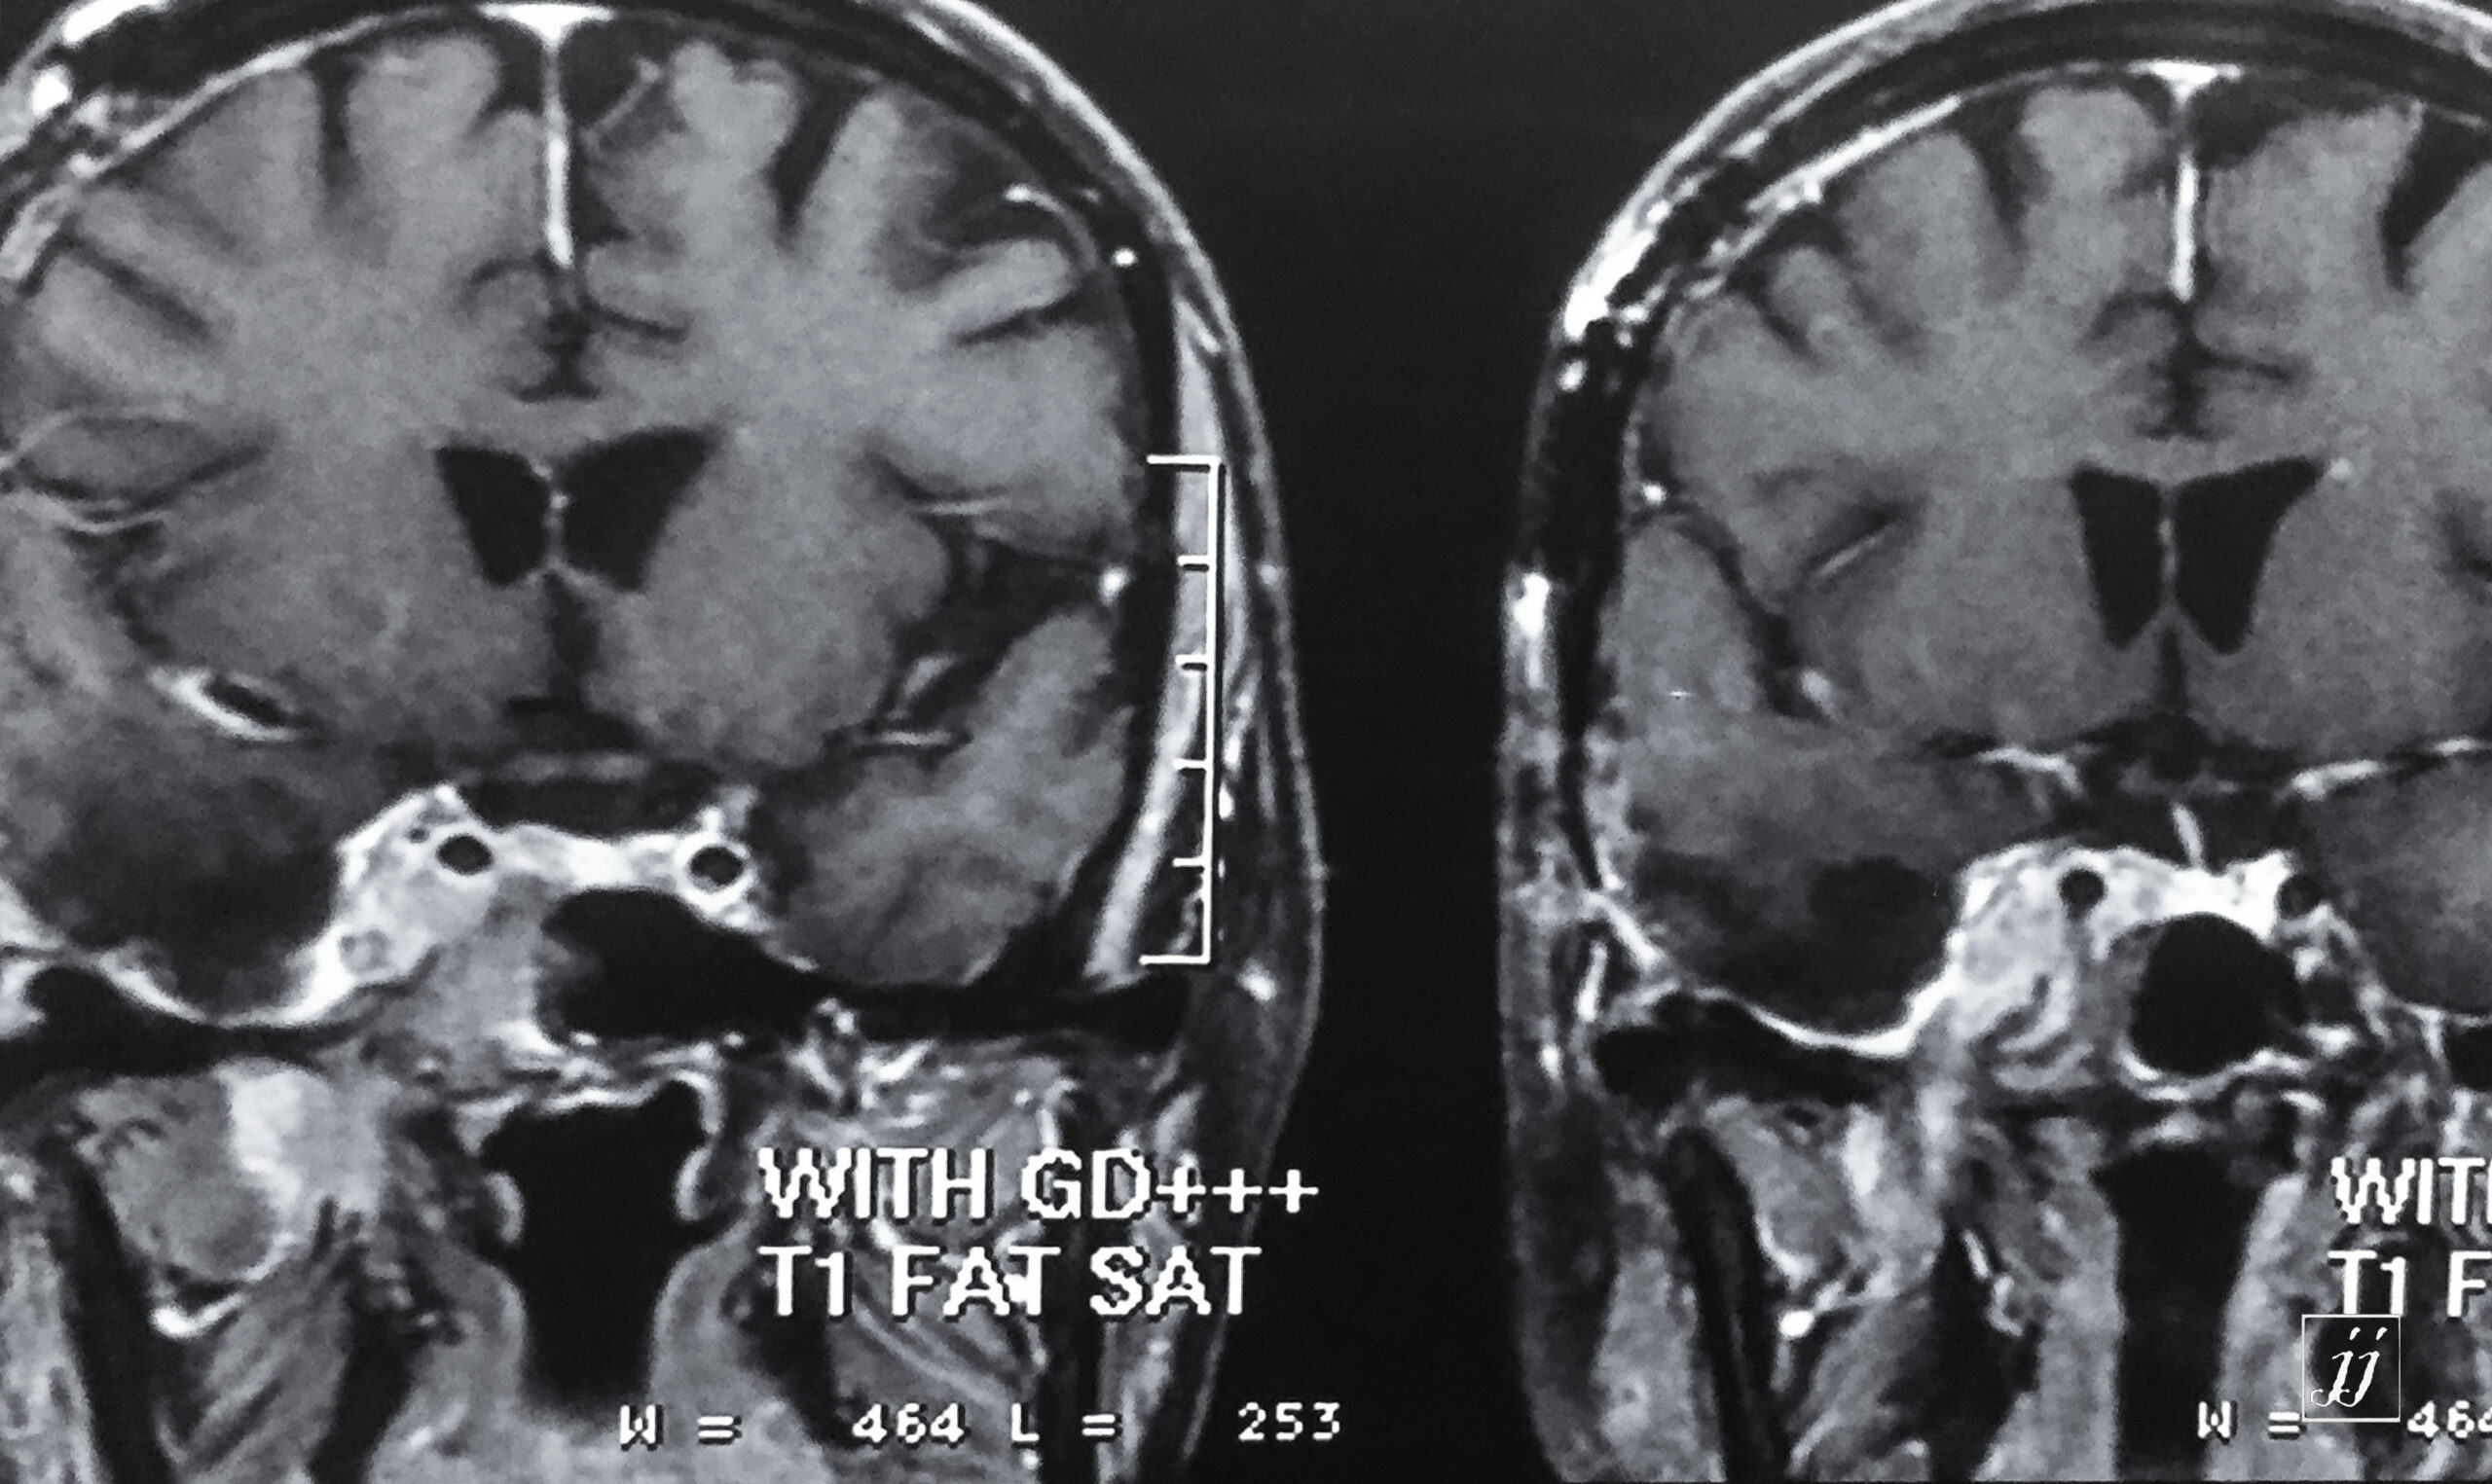

Brain- right para selar mass in casing carotid (2)